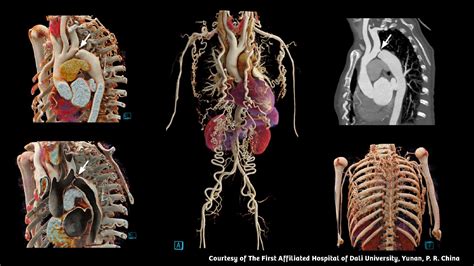

The primary purpose of using a contrast agent during a Computed Tomography (CT) scan is to make specific areas "pop" on the monitor. Without contrast, some organs—like those in the abdomen—might look similar in density, making it difficult to spot subtle abnormalities. When the Ct Contrast agent, which often contains iodine or barium, enters your system, it absorbs X-rays differently than the surrounding tissue. This interaction creates a distinct visual difference in the final image, effectively "highlighting" the targeted area.

Vascular Imaging To map arteries and veins to identify blockages or aneurysms.

Inflammation/Infection To identify areas of increased blood flow associated with active infection.

Trauma Assessment To quickly identify internal bleeding or damage to organs.